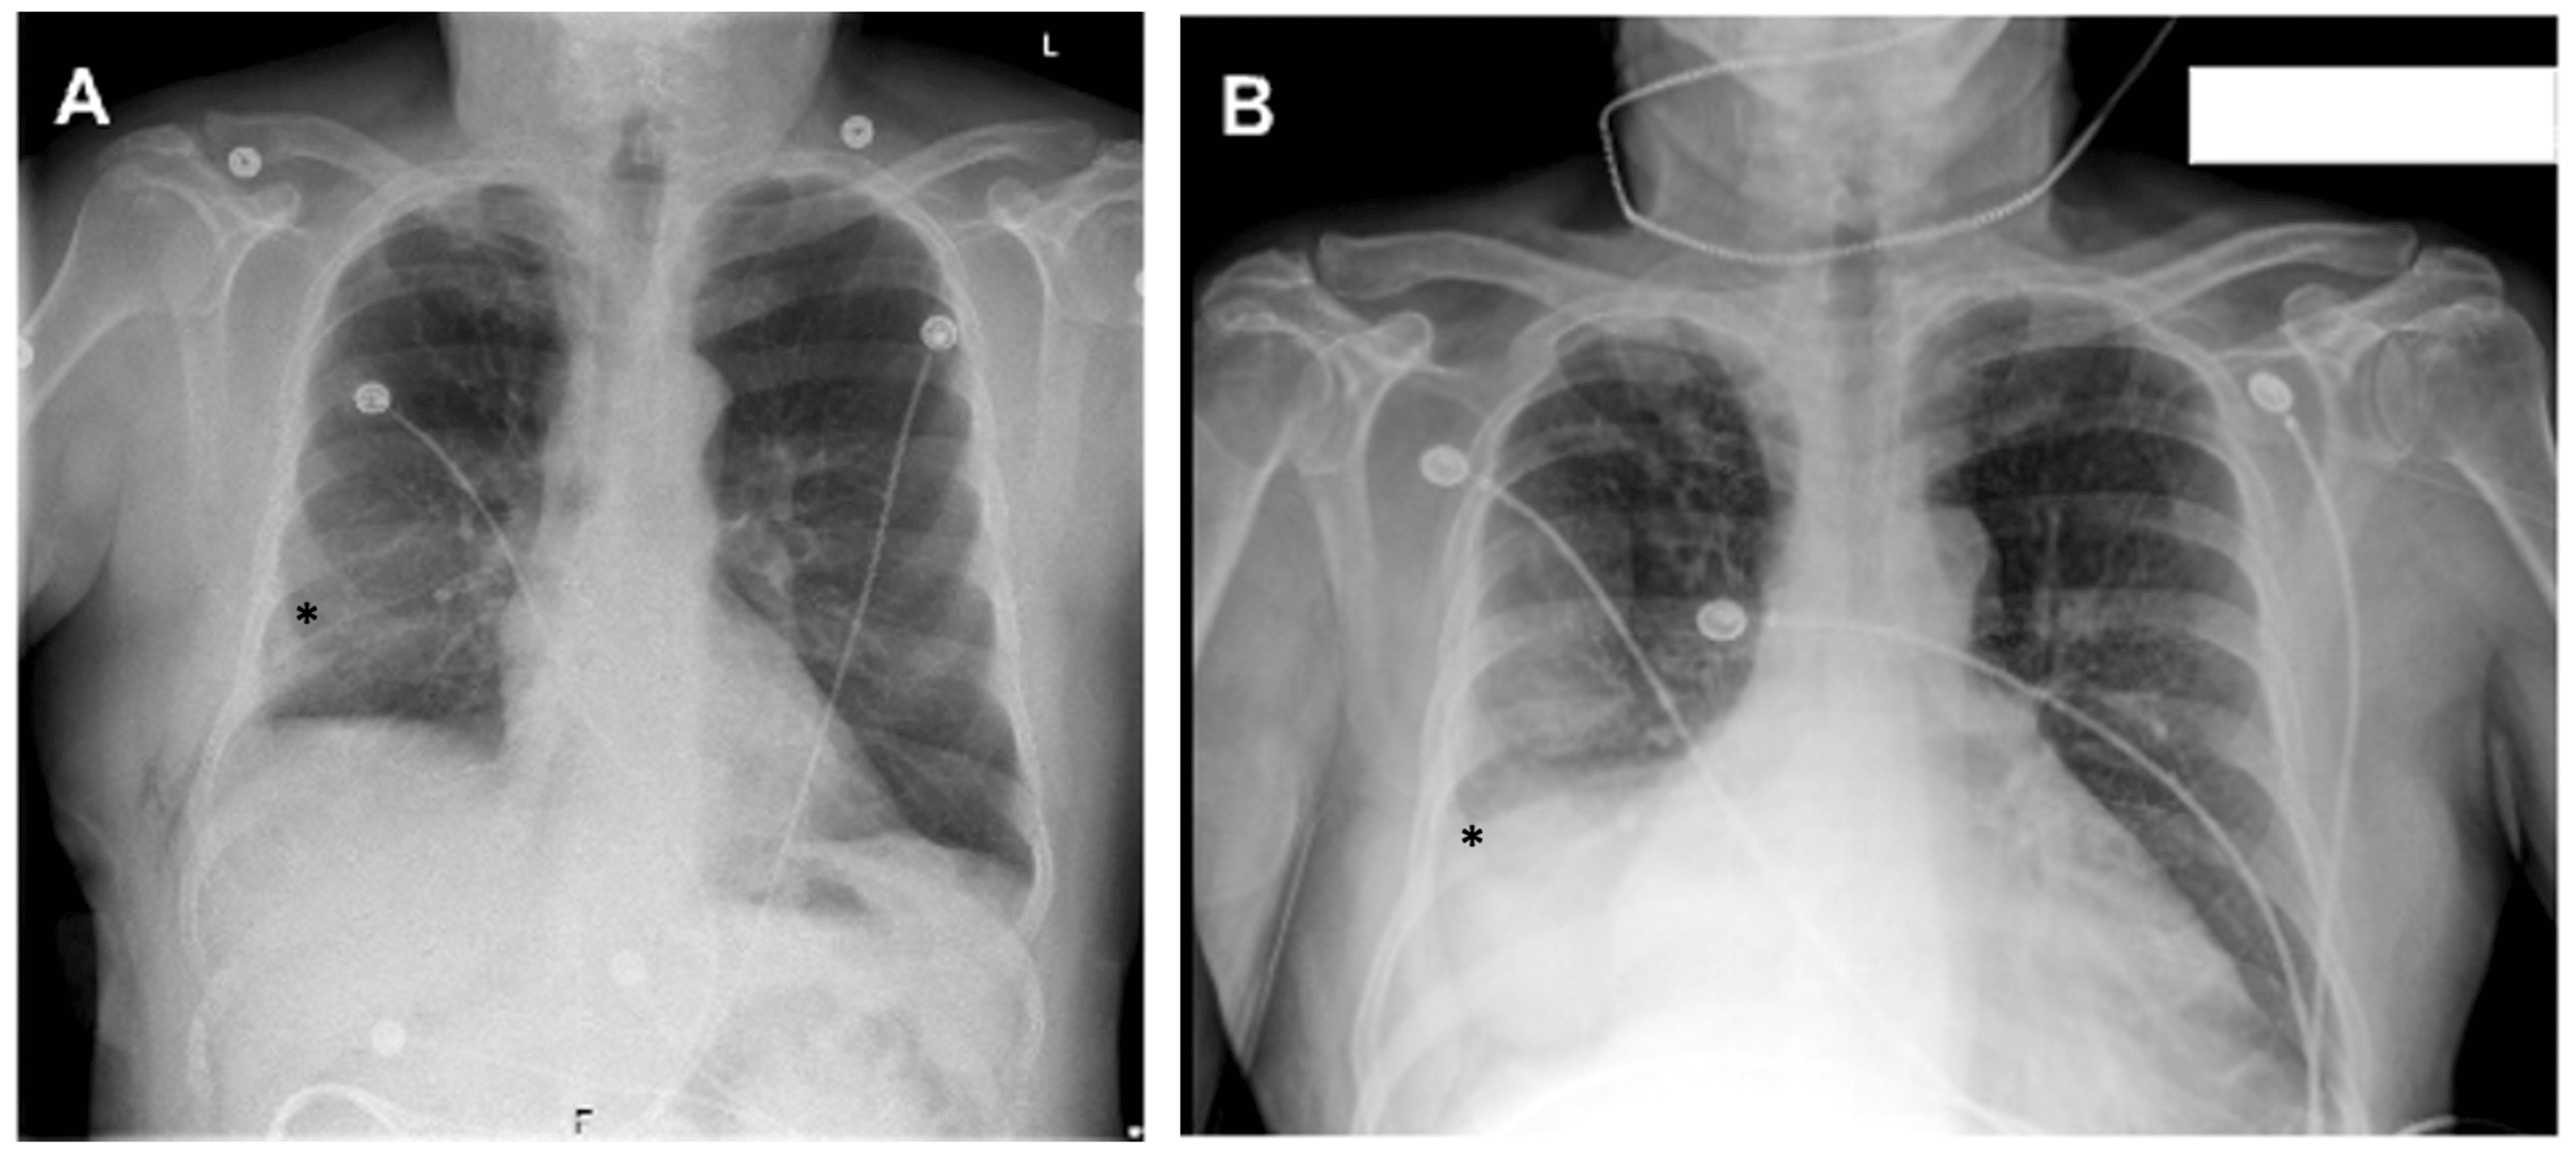

Chest Xray showed subsegmental bibasilar atelectasis Download Chest X Ray Subsegmental Atelectasis In most cases affecting adults, atelectasis will appear in the lower left lobe of the lungs. Find out if it is serious, how to. Learn about the possible causes, how. Atelectasis is a condition where part of the lung collapses due to fluid, mucus or blockage. Your healthcare provider may use a computed tomography (ct) scan to get. Learn about. Chest X Ray Subsegmental Atelectasis.

Chest Xray on admission showing subsegmental atelectasis in the left Chest X Ray Subsegmental Atelectasis Atelectasis is a condition where part of the lung collapses due to fluid, mucus or blockage. Your healthcare provider may use a computed tomography (ct) scan to get. Learn about the different mechanisms, morphologies and anatomical extents of lung atelectasis, a condition where. In most cases affecting adults, atelectasis will appear in the lower left lobe of the lungs. If. Chest X Ray Subsegmental Atelectasis.